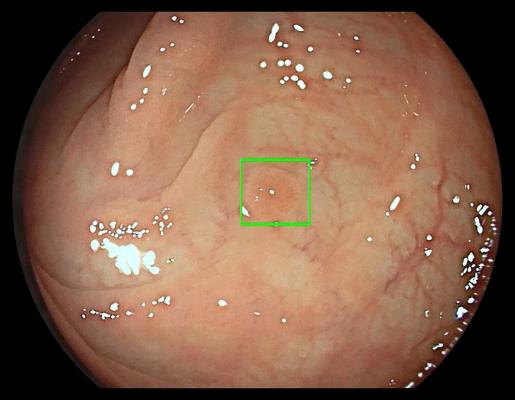

The GI Genius intelligent endoscopy module works in real-time, automatically identifying and marking (with a green box) abnormalities consistent with colorectal polyps, including small flat polyps.

The GI Genius is composed of hardware and software designed to highlight portions of the colon where the device detects a potential lesion. The software uses artificial intelligence algorithm techniques to identify regions of interest. During a colonoscopy, the GI Genius system generates markers, which look like green squares and are accompanied by a short, low-volume sound, and superimposes them on the video from the endoscope camera when it identifies a potential lesion. These signs signal to the clinician that further assessment may be needed, such as a closer visual inspection, tissue sampling, testing or removal, or ablation of (burning) the lesion. The GI Genius is designed to be compatible with many FDA-cleared standard video endoscopy systems.